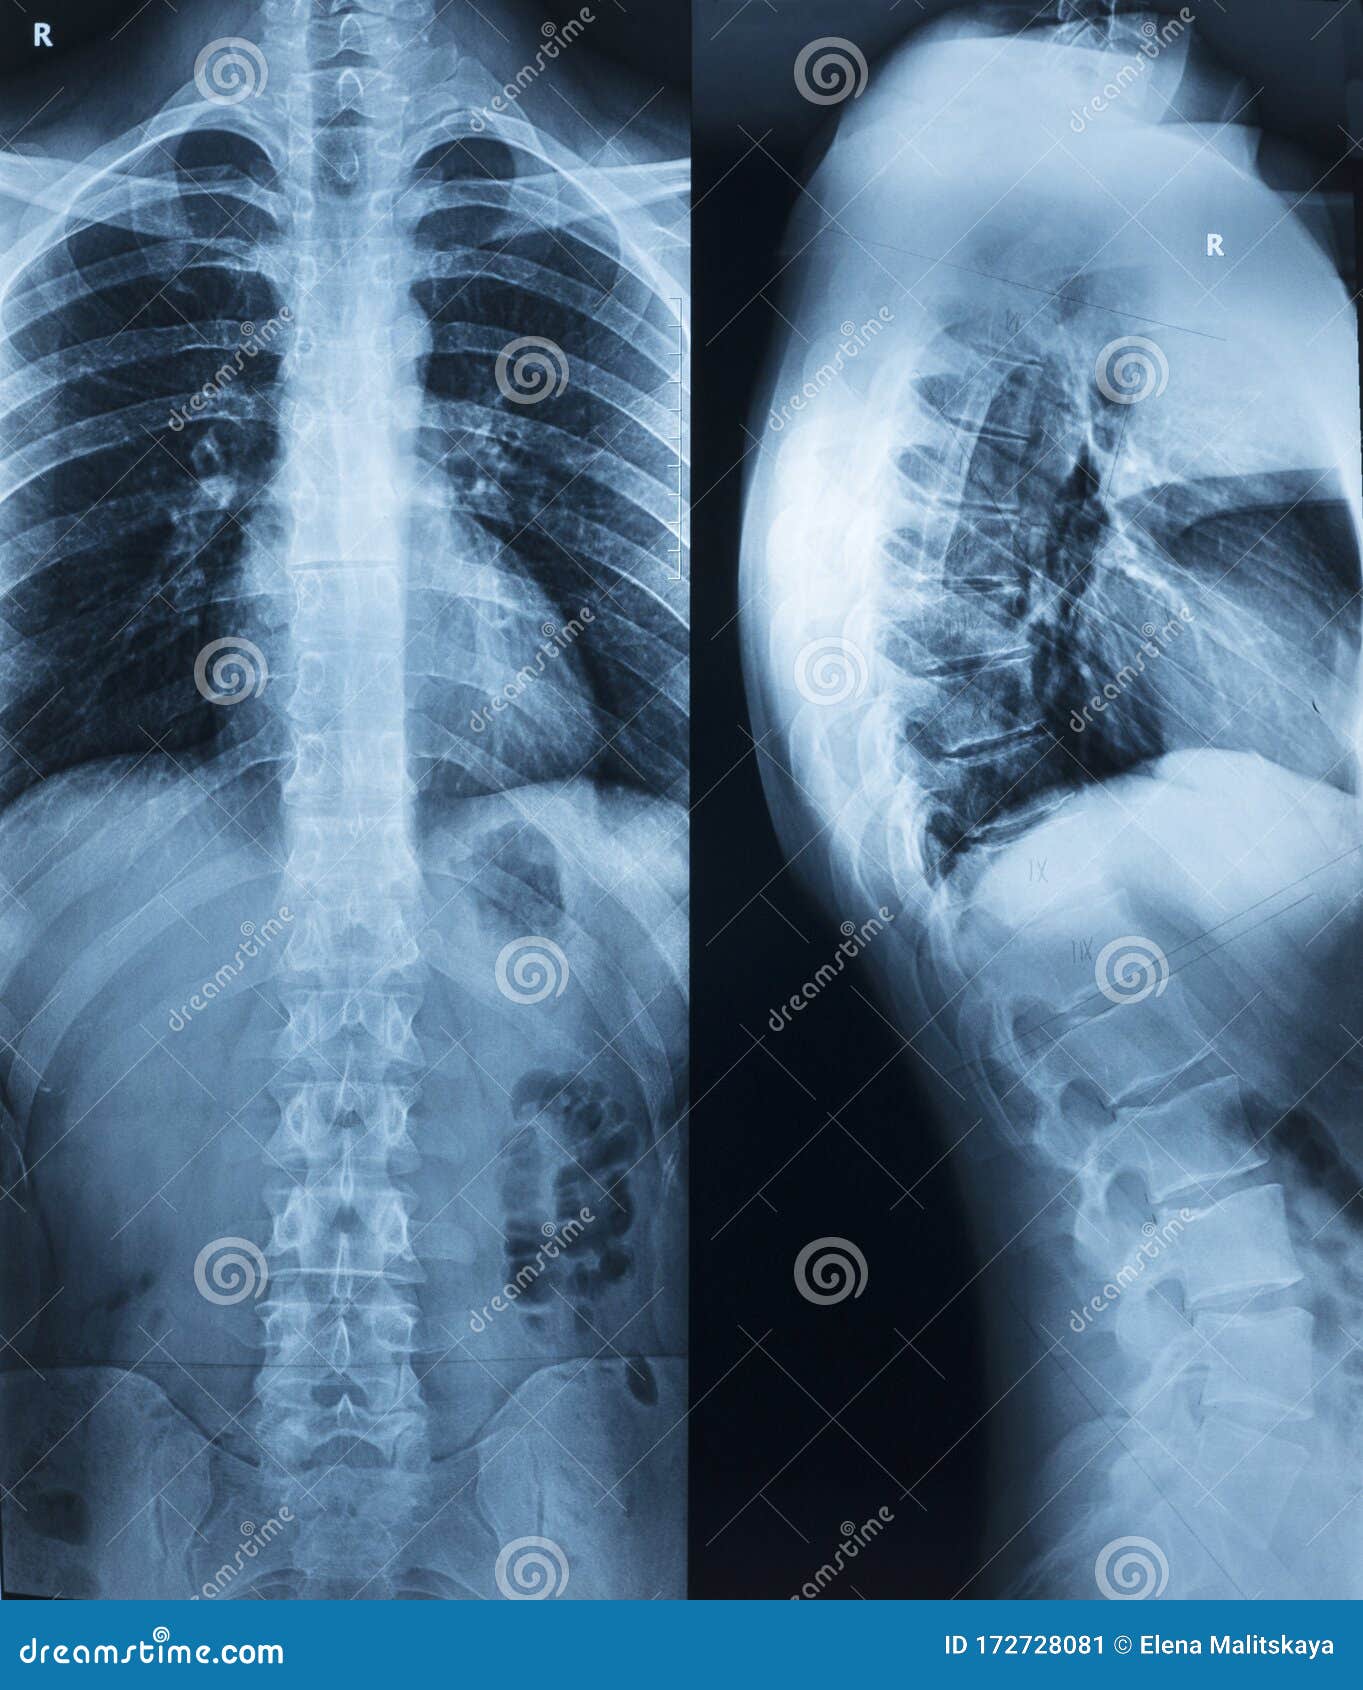

Рентген шейных позвонков при спина бифида

Раздел: Фотозарисовки